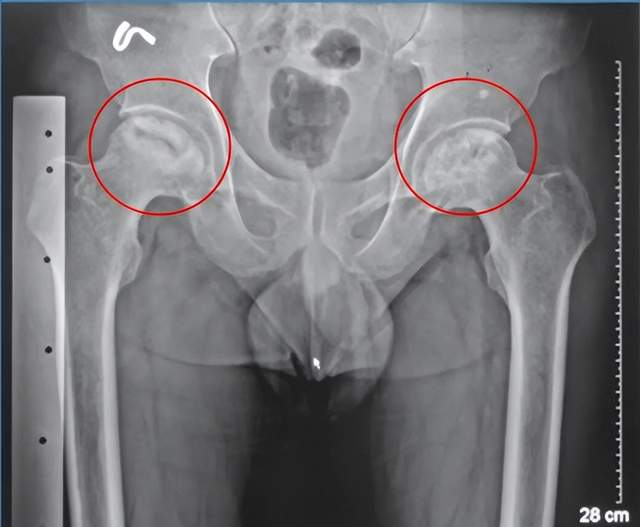

据统计,我国有超过800万非创伤性股骨头坏死患者。有研究表明,股骨头坏死好发于28岁至65岁之间,男女比例约为3.1:1,有超过70%的患者出现双侧病变。

如因暴力撞击引起股骨颈骨折、髋关节脱位等,因为骨折及脱位影响了股骨头的血液供应,缺血的股骨头极易发生坏死。创伤性股骨头缺血坏死发生与否、以及范围的大小,主要取决于血管破坏程度和侧支循环的代偿能力。

如果您是上述三种高危人群,又出现髋部疼痛不适的症状,应及时前往医院检查。医生一般会对您进行髋部的X光检查或磁共振成像(MRI)检查。MRI是目前早期诊断股骨头坏死的最佳检查方式。